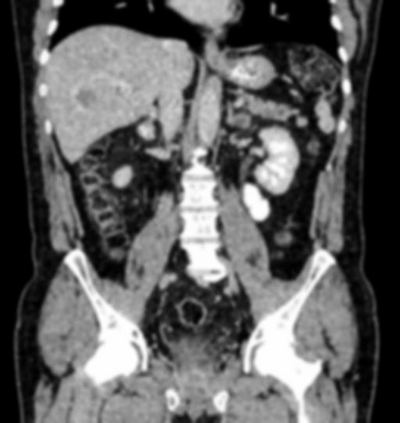

Due to the constraints of the imaging device and high cost in operation time, computer tomography (CT) scans are usually acquired with low intra-slice resolution. Improving the intra-slice resolution is beneficial to the disease diagnosis for both human experts and computer-aided systems. To this end, this paper builds a novel medical slice synthesis to increase the between-slice resolution. Considering that the ground-truth intermediate medical slices are always absent in clinical practice, we introduce the incremental cross-view mutual distillation strategy to accomplish this task in the self-supervised learning manner. Specifically, we model this problem from three different views: slice-wise interpolation from axial view and pixel-wise interpolation from coronal and sagittal views. Under this circumstance, the models learned from different views can distill valuable knowledge to guide the learning processes of each other. We can repeat this process to make the models synthesize intermediate slice data with increasing inter-slice resolution. To demonstrate the effectiveness of the proposed approach, we conduct comprehensive experiments on a large-scale CT dataset. Quantitative and qualitative comparison results show that our method outperforms state-of-the-art algorithms by clear margins.